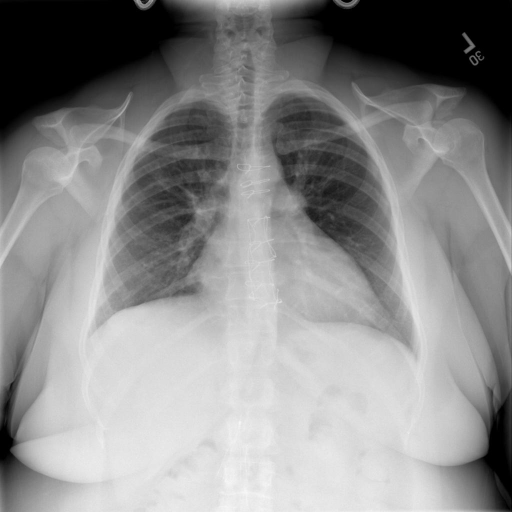

# 本文贡献  - 借助ChatGPT以及公开的数据集,我们构造了一个`X光影像-诊断报告`对的医学多模态数据集; # 数据集 - [MIMIC-CXR](https://physionet.org/content/mimic-cxr-jpg/2.0.0/)是一个公开可用的胸部X光片数据集,包括377,110张图像和227,827个相关报告。 - [OpenI](https://openi.nlm.nih.gov/faq#collection)是一个来自印第安纳大学医院的胸部X光片数据集,包括6,459张图像和3,955个报告。 在上述工作中,报告信息都为非结构化的,不利于科学研究。为了生成合理的医学报告,我们对两个数据集进行了预处理,并最终得到了可以用于训练的**英文报告**。除此之外,为了更好的支持中文社区发展,借助ChatGPT的能力,我们将英文报告进行了中文翻译,并最终形成了可用于训练的数据集。 |数据集|数量|下载链接| |:-|:-|:-| |MIMIC-CXR-zh|-|-| |OpenI-zh|6,423|[诊疗报告](./data/Xray/openi-zh.json) 、[X光影像](https://pan.baidu.com/s/13GBsDMKf6xBZBSHpoWH_EA?pwd=k9sh)| # 快速上手 1. 安装环境 ```bash # 安装依赖 pip install -r requirements.txt # 国内换源安装依赖 pip install -i https://mirrors.aliyun.com/pypi/simple/ -r requirements.txt ``` 此时默认会安装`deepspeed`库(支持`sat`库训练),此库对于模型推理并非必要,同时部分`Windows`环境安装此库时会遇到问题。 如果想绕过`deepspeed`安装,我们可以将命令改为: ```bash # 安装依赖 pip install -i https://mirrors.aliyun.com/pypi/simple/ -r requirements_wo_ds.txt # 安装SwissArmyTransformer pip install -i https://mirrors.aliyun.com/pypi/simple/ --no-deps "SwissArmyTransformer>=0.3.6" ``` 2. 模型推理 CLI推理: ```python python cli_demo.py --from_pretrained checkpoints/finetune-XrayGLM-05-25-01-04 --prompt_zh '详细描述这张胸部X光片的诊断结果' ``` 更多[参数](https://github.com/WangRongsheng/XrayGLM/blob/main/cli_demo.py#L16) # 效果展示 诊断: |X光影像|诊疗报告(医生)|XrayGLM| |:-|:-|:-| ||根据X射线图像,心脏大小正常,肺部看起来很清晰。已经排除了肺炎、积液、水肿、气胸、腺病、结节或肿块的存在。该发现表明一切正常。换句话说,总体印象是胸部正常。|X光片显示,心脏大小正常。肺部没有气胸或胸腔积液的证据。骨骼结构看起来没有任何异常。总的来说,X光片表明没有发现急性心肺疾病的迹象。| ||X光图片显示没有扭曲的区域、可疑的骨质不透明度或胸腺积液。心脏大小轻微增大,但非常稳定。此外,没有气胸的证据,肺野也正常。总体来说,X光片显示没有急性心脏异常,但要注意轻微的心脏扩大。|X光片显示,心脏大小正常。肺部和纵隔轮廓清晰,没有气胸或胸腔积液的证据。骨骼结构完整,没有任何急性异常。| ||心影形态在正常范围内。没有急性骨质异常。有可能出现没有明显的吸水或肺实质状况的线索。没有大面积积液或气胸。有可能怀疑其有误吸或肺实质问题。为了确诊和治疗,可能需要进行适当的影像学随访。|心脏大小正常,肺部和纵隔轮廓清晰。没有急性异常或活动受限的证据。没有任何明显的气胸、胸腔积液或肺不张的迹象。此外,也没有发现任何局灶性骨质异常或其他急性疾病。| 多轮对话: |X光影像|诊疗报告(医生)| |:-|:-| ||右侧主动脉突出观察到。心脏大小正常。胸部未发现明显的肺气肿、胸膜积液或可疑的肺部病变。报告指出已知右侧主动脉情况正常。| ```bash >> X光影像路径:./data/Xray/861_1.png >> 用户:这是一张什么图? >> XrayGLM:这张图片显示的是一张肺部检查的X光片。 >> 用户:请描述这张胸部X光片的诊断结果 >> XrayGLM:心脏大小正常,肺部清晰。没有急性心肺疾病的证据。 >> 用户:是否存在肺气肿? >> XrayGLM:没有肺气肿。心脏大小正常,肺部清晰。没有发现急性心肺疾病的证据。 >> 用户:平时饮食该注意什么? >> XrayGLM:饮食应该健康,均衡。建议增加蛋白质的摄入量,因为蛋白质有助于维持肌肉和骨骼的健康。多食用蔬菜、水果、全谷物以及健康的脂肪来源如橄榄油、鱼类等可以帮助获得足够的维生素和矿物质。此外,避免过度饮酒或吸烟,这些习惯可能会对心脏健康产生负面影响。 ``` # 项目致谢 1. [VisualGLM-6B](https://github.com/THUDM/VisualGLM-6B)为我们提供了基础的代码参考和实现; 2. [MiniGPT-4](https://github.com/Vision-CAIR/MiniGPT-4)为我们这个项目提供了研发思路; 3. ChatGPT生成了高质量的中文版X光检查报告以支持XrayGLM训练; 4. [gpt_academic](https://github.com/binary-husky/gpt_academic)为文档翻译提供了多线程加速; 5. [MedCLIP](https://github.com/RyanWangZf/MedCLIP) 、[BLIP2](https://huggingface.co/docs/transformers/main/model_doc/blip-2) 、[XrayGPT](https://github.com/mbzuai-oryx/XrayGPT) 等工作也有重大的参考意义;  这项工作由[澳门理工大学应用科学学院](https://www.mpu.edu.mo/esca/zh/index.php)硕士生[王荣胜](https://github.com/WangRongsheng) 、[段耀菲](https://github.com/IsBaSO4) 、[李俊蓉](https://github.com/lijunrong0815)完成,指导老师为檀韬副教授、[彭祥佑](http://www.patrickpang.net/)老师。 *特别鸣谢:[USTC-PhD Yongle Luo](https://github.com/kaixindelele) 提供了有3000美金的OpenAI账号,帮助我们完成大量的X光报告翻译工作 # 免责声明 本项目相关资源仅供学术研究之用,严禁用于商业用途。使用涉及第三方代码的部分时,请严格遵循相应的开源协议。模型生成的内容受模型计算、随机性和量化精度损失等因素影响,本项目无法对其准确性作出保证。即使本项目模型输出符合医学事实,也不能被用作实际医学诊断的依据。对于模型输出的任何内容,本项目不承担任何法律责任,亦不对因使用相关资源和输出结果而可能产生的任何损失承担责任。 # 项目引用 如果你使用了本项目的模型,数据或者代码,请声明引用: ```bash @misc{wang2023XrayGLM, title={XrayGLM: The first Chinese Medical Multimodal Model that Chest Radiographs Summarization}, author={Rongsheng Wang, Yaofei Duan, Junrong Li, Patrick Pang and Tao Tan}, year={2023}, publisher = {GitHub}, journal = {GitHub repository}, howpublished = {\url{https://github.com/WangRongsheng/XrayGLM}}, } ``` # 使用许可 此存储库遵循[CC BY-NC-SA](https://creativecommons.org/licenses/by-nc-sa/4.0/) ,请参阅许可条款。